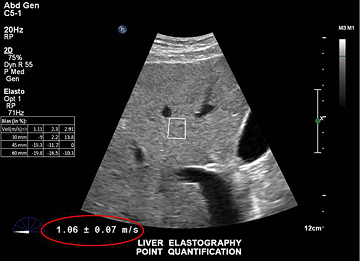

ElastPQ è un metodo facile da usare per ottenere i valori della rigidità dei tessuti epatici di una ROI predefinita. Utilizzando l'imaging in tempo reale come guida, la ROI viene posizionata sull'area di interesse e i dati relativi alla rigidità dei tessuti, ad esempio AVG, MEAN e IQR, vengono generati e visualizzati in pochi secondi. È possibile registrare più campioni e generare un referto sulle condizioni del tessuto epatico a partire dai risultati.

La misurazione della rigidità del tessuto epatico viene eseguita in pochi secondi con una semplice scansione non invasiva